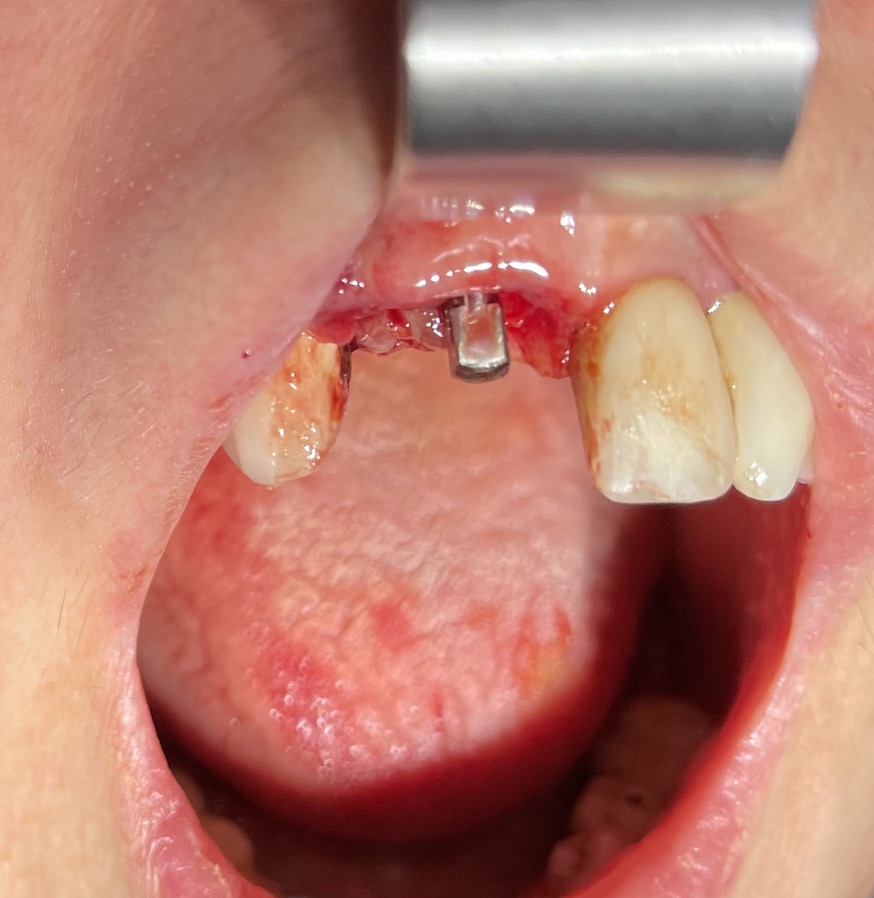

N° impianti inseriti : 2

Zona dentale: 11 12

Situazione estrattiva: postestrattivi immediati

Sequenza frese: solo lanceolata

Sequenza maschiatori: diametro 4 mm

Descrizione intervento

Complicanze: assenti